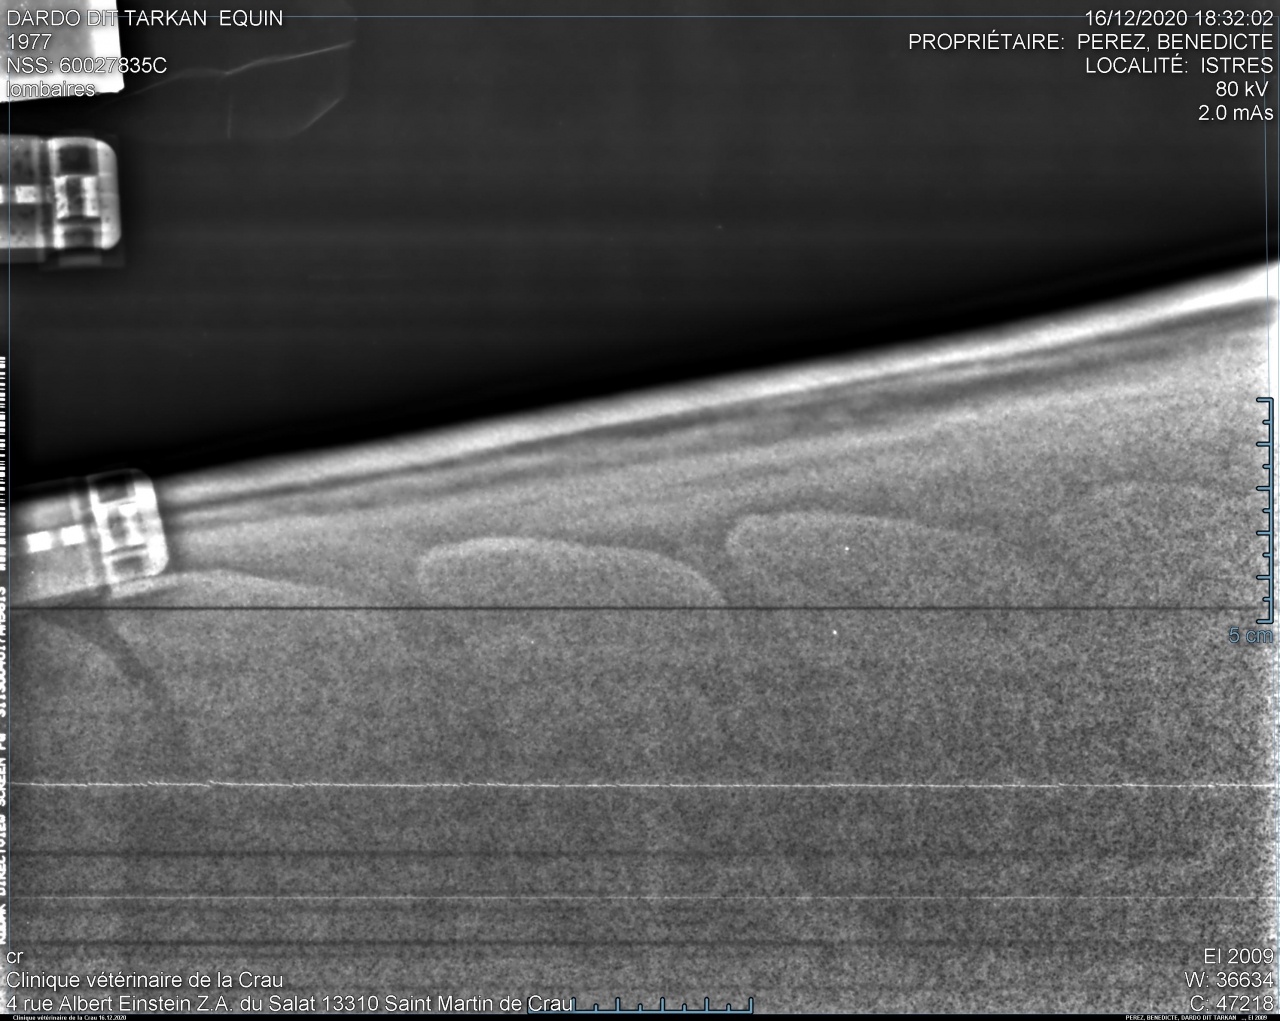

| Dire merci | bon... sans suspens aucun voilà les radios de Takhan : garrot très bien : ![]() ![]() T15/16 : la cata ![]() ![]() puis les lombaires.... acceptable mais pas génial : ![]() ![]() Je le savais mais ça fait un choc tout de meme... Je débriefe avec la véto aujourd'hui pour savoir ce qu'on fait, méso, laser? bref on va voir... Il est très très contracturé sur le dos donc déjà on va traiter ça avec mon osteo qui est aussi shiatsu girl et masseuse. Ça fait chier quand meme... |

| Dire merci | Alors oui dawa , sur les radios du garrot, tu vois que les vertèbres sont bien écartées, l'os parait visuellement "propre". Tout va bien. Sur les lombaires c'est un gros plan sur le haut des vertèbres et tu vois que l'espacement entre les vertèbres est mince mais existant. Rien ne se touche. On considère que c'est problématique quand l'espacement est en dessous de 4mm. Pour le dos, donc T15/T16 (sous mes fesses pour faire simple), tu vois que les vertèbres se touchent, et en plus, sur un coté de la radio tu vois une petite tache blanche entre les 2 vertèbres c'est ce qu'on appelle le chevauchement. Y pas encore de pont osseux donc on peut pas dire qu'il soit soudé encore.Pas complètement quoi. |